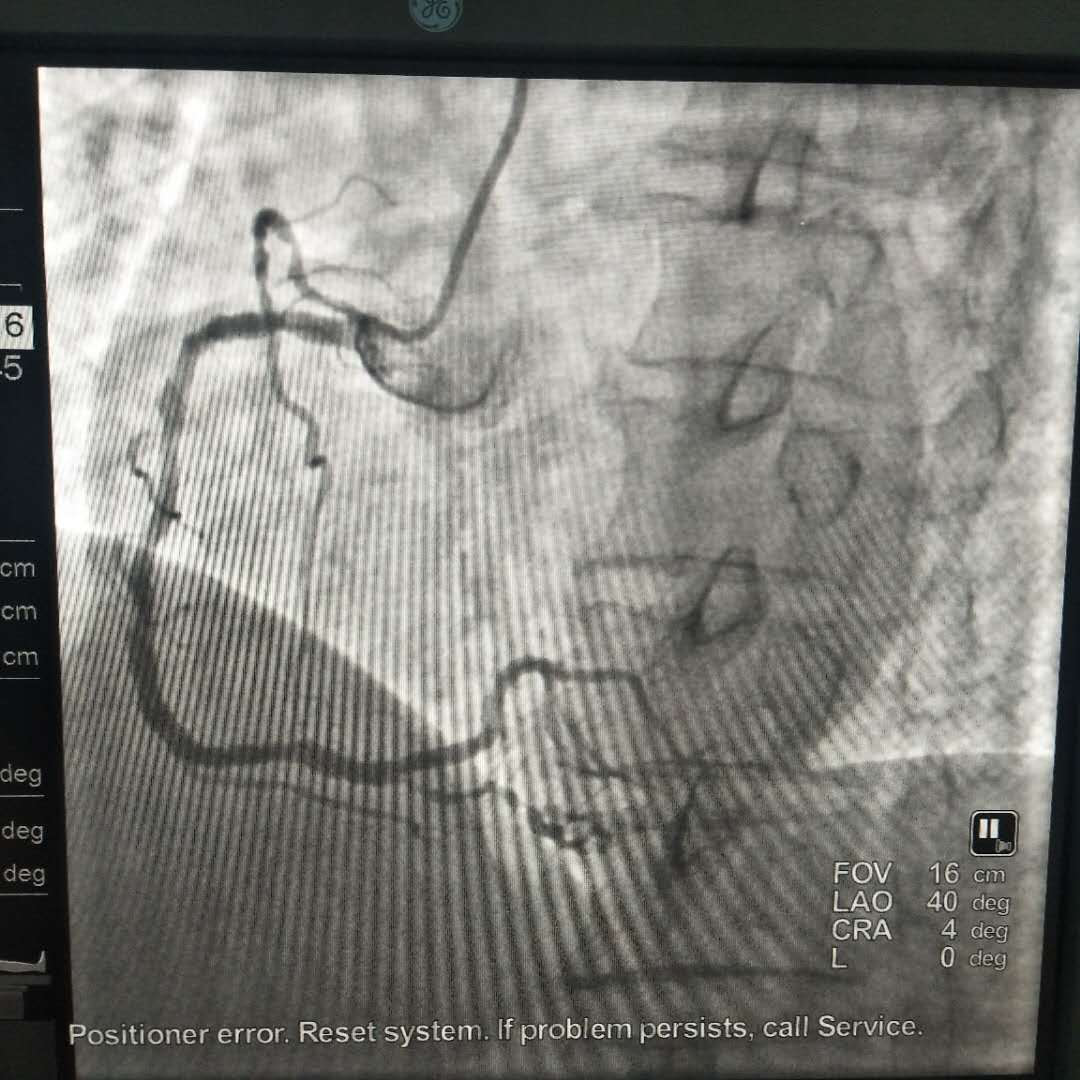

造影结果:

左冠:前降支中段次全闭塞并见血栓影,远段狭窄70%;回旋支近中段狭窄85%并见血栓影,远段弥漫狭窄80%-90%,OM1中段狭窄90%。

右冠:近中段弥漫狭窄60%-70%,后降支弥漫狭窄90%-95%。

结论:冠心病,三支血管病变。建议行PCI或CABG治疗。